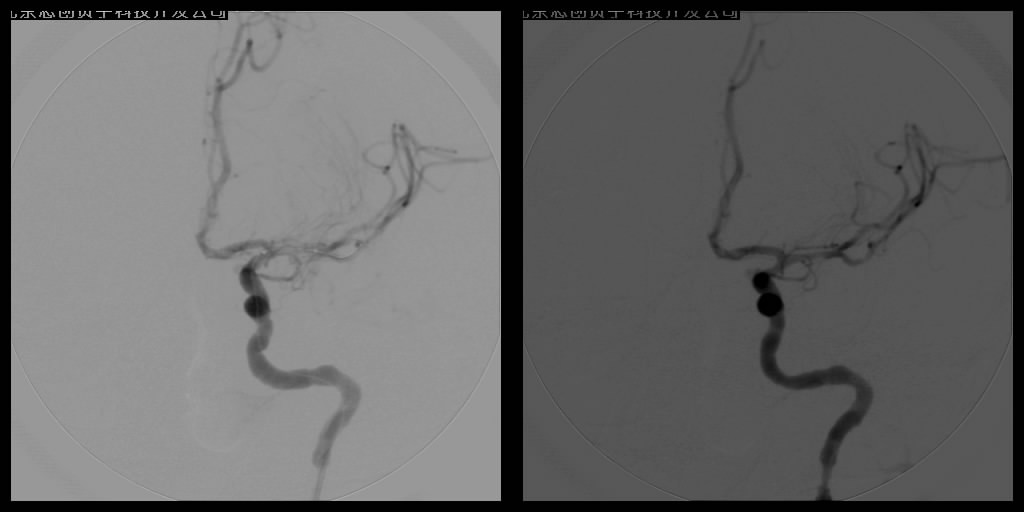

腦梗塞微創(chuàng)介入治療——數(shù)字減影血管造影(DSA)介入治療

血管球囊擴(kuò)張成形術(shù)和血管內(nèi)支架植入成形術(shù)已經(jīng)成為治療腦缺血、腦梗塞十分重要的手段。手術(shù)操作時在DSA監(jiān)控下,將導(dǎo)引管經(jīng)主動脈插到供應(yīng)顱腦的血管——頸動脈或椎動脈內(nèi),再置放支架,達(dá)到擴(kuò)開狹窄段血管、順性行血流再建的目的,所用支架可分為球囊擴(kuò)張式支架和自膨式支架。DSA系統(tǒng)輔助下的動脈血管成形術(shù)不但能清晰明確地了解影像病變,而且在造影過程中就可了解血管內(nèi)血流、血管壁等情況,全面判斷血管結(jié)構(gòu)及功能變化,為確診和治療提供了可靠的依據(jù),已在臨床上取得了良好的療效。